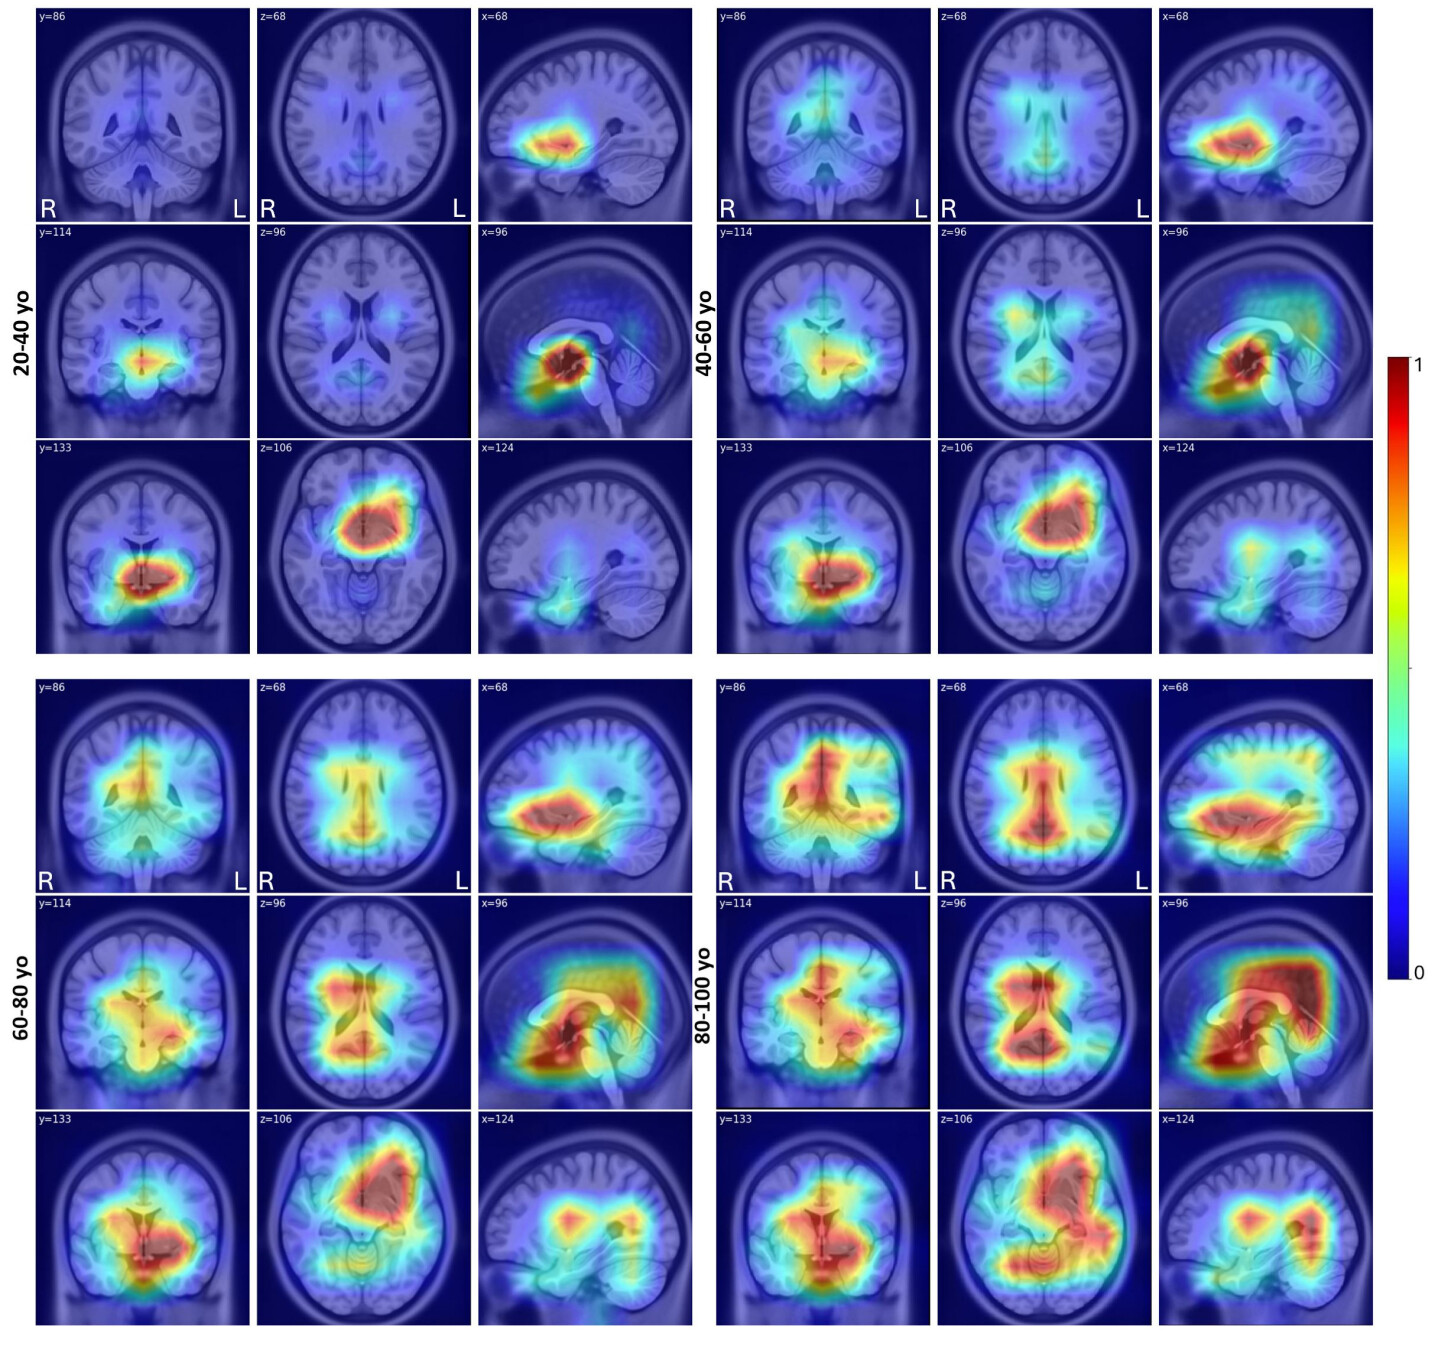

As an exploratory study, we computed the mean values from the population-averaged Grad-RAM heatmaps within 116 brain parcellations based on the AAL116 atlas. Upon inspecting the population-averaged Grad-RAM results across different age groups, the ResNet50-highRez model highlighted fairly consistent regions of interest across the age groups, with virtually no differences between sexes. Specifically, for all age groups, the main areas the model focuses on are in the left hemisphere (in order of decreasing magnitude, with the mean saliency greater than 0.8): pallidum, amygdala, and putamen. The younger population (20\sim40 yo) has a high saliency concentration in the left hippocampus and pallidum. As the population ages, several other areas become more involved, especially for the population above 80 yo, and these include the right pallidum, thalamus, caudate, left parahippocampal gyrus, left hippocampus, posterior cingulum, vermis, and left frontal orbital gyrus. Based on the observation, with aging, the ResNet50-highRez model focuses on wider and more diverse regions of interest while the primary focus is still on subcortical regions. A visual inspection of the averaged Grad-RAMs (see Fig. 4) further confirms our results, showing the younger population (20\sim40 yo) having a more concentrated activation area, and the older population expanding the activation area in the subcortical regions, ventricles, and the cortex.

Refer to caption

Figure 4: Averaged Grad-RAM heatmaps produced from the ResNet 50-highRez model based on the healthy control test set for the age groups of 20-40 yo, 40-60 yo, 60-80 yo, and 80-100 yo.

In contrast to ResNet50-highRez, the RNC-highRez model showed more distinct Grad-RAM activation patterns across different age groups. For the 20\sim40 yo group, the activated areas from the DL model are on the right parietal and lateral frontal lobe, including (in the order of decreasing magnitude, with the mean saliency greater than 0.8) inferior parietal, right postcentral, precentral, supramarginal, and angular gyrus, and right paracentral lobule. For the 40\sim60 yo group, the model shifts the attention with a focus towards the left lateral frontal lobe, particularly the frontal inferior operculum, frontal inferior triangularis, rolandic operculum, and with a broader and relatively weaker focus on areas around it, such as the left insula. Finally, the 60\sim80 yo group and the 80+ yo group have highly similar activation patterns, focusing on subcortical regions and to a lesser extent, the left lateral frontal lobe. The main regions of interest remain on the left hemisphere, including (in the order of decreasing magnitude, with the mean saliency greater than 0.8) the thalamus, pallidum, putamen, hippocampus, amygdala, caudate, and vermis. A visual inspection (see Fig. 5) confirms these findings from the parcellation-wise mean Grad-RAM values and suggests that the younger population (20\sim40 yo) has more activation in the lateral frontal and parietal lobes, shifting towards the left hemisphere’s subcortical regions and lateral ventricles along with the aging process.

Similar to the case of ResNet50-highRez, the RNC-highRez model also did not demonstrate drastic Grad-RAM pattern differences between male and female aging although some nuanced distinctions in the strengths of activation were present for across age groups and within the same age groups. On average, the right parietal inferior lobe, right angular gyrus, right paracentral lobule, right parietal superior lobe, and left frontal superior lobe, are about 40% more activated for males, with the contribution mainly from the 20\sim40 group.